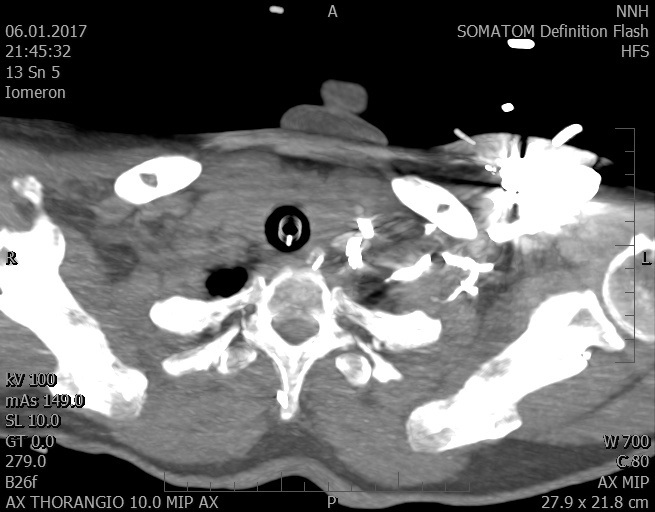

Video 2 - Echokardiograficky byla zjištěna těžká dysfunkce dilatační levé komory s nezvětšenou pravou komorou.Pro nejasnou příčinu zástavy jsme provedli i vyšetření výpočetní tomografií (CT), které vyloučilo plicní embolizaci (série 1 - soubory na konci článku). V den přijetí při přetrvávající oběhové nestabilitě byla nemocná opakovaně defibrilována pro fibrilaci komor se stabilizací rytmu po podání amiodaronu a mesocainu. Dle hemodynamických měření se jednalo o těžký kombinovaný šok. Vstupní laboratorní vyšetření bylo bez větších pozoruhodností. Posléze jsme doplnili anamnézu od příbuzných a zjistili, že pacientka užila do dvou hodin před srdeční zástavou první tabletu amoxicilinu na lehký respirační infekt. Při nevýtěžnosti vstupních vyšetření a nových anamnestických informacích jsme doplnili 14 hodin po kolapsu vyšetření koncentrace tryptázy v séru, která byla extrémně zvýšena (tabulka 2), což nás vedlo k podezření na anafylaxi.